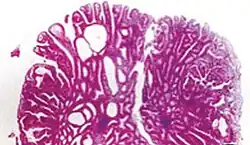

Sessile serrated adenoma (SSA)[17]

• Basal dilation of the crypts

• Basal crypt serration

• Crypts that run horizontal to the basement membrane (horizontal crypts)

• Crypt branching.